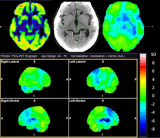

• 新型Tau PET示踪剂具有高灵敏度和特异性,可识别早期阿尔茨海默病

根据《The Journal of Nuclear Medicine》9月刊上发表的一项研究表明,一种新型Tau PET放射性示踪剂18F-SNFT-1被发现比现有的Tau PET放射性示踪剂更能在早期阶段识别阿尔茨海默病。在正面比较中,与临床使用的第二代Tau PET示踪剂相比,18F-SNFT-1具有更好的脑部药代动力学,并且对阿尔茨海默病Tau蛋白病变显示出更高的亲和力和选择性。

新型Tau PET示踪剂具有高灵敏度和特异性,可识别早期阿尔茨海默病

根据《The Journal of Nuclear Medicine》9月刊上发表的一项研究表明,一种新型Tau PET放射性示踪剂18F-SNFT-1被发现比现有的Tau PET放射性示踪剂更能在早期阶段识别阿尔茨海默病。在正面比较中,与临床使用的第二代Tau PET示踪剂相比,18F-SNFT-1具有更好的脑部药代动力学,并且对阿尔茨海默病Tau蛋白病变显示出更高的亲和力和选择性。 2023-10-12 放射性示踪剂